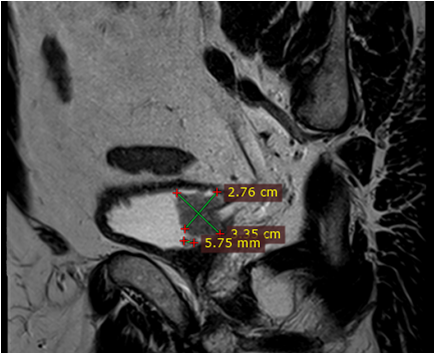

Під час проведення профілактичного УЗД у нього було виявлено пухлину правої нирки.

Основний: T-r (2 пухлини) правої нирки сT2 N0 M0 Gх ст ІI, кл.гр 2.